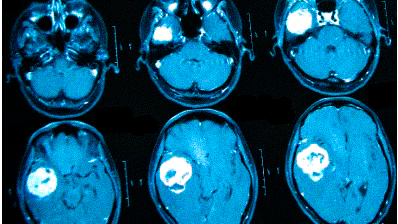

Для оценки опухолевых новообразований и определения стадии, включая метастатическое распространение, используется МРТ с контрастированием. Препараты на основе хелатов гадолиния помогают выявить даже небольшие опухоли в труднодоступных местах, что делает этот метод эффективным, если другие визуализационные методы дали неоднозначные результаты. При подозрении на сосудистые заболевания головного мозга рекомендуется ангиорежим.

МРТ головного мозга может выявить:

- опухолевые процессы (доброкачественные и злокачественные);

- последствия травм (гематомы, кровоизлияния);

Онкологи подчеркивают, что при нарастающих головных болях и других необъяснимых симптомах (обмороках, ухудшении памяти, выпадении полей зрения, давлении на глазные яблоки и др.) необходимо в первую очередь исключить опухолевую патологию.

Что покажет МРТ головы с контрастом